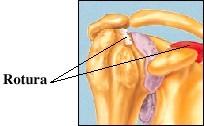

Sindrome de pinzamiento Subacromial Síndrome del roce o impigement: irritación mecánica del manguito de los tendones rotadores del hombro por uno o más de los diferentes componentes del arco acromial : acromion, articulación acromioclavicular, ligamento acromiocoracoideo y apófisis coracoides. • NEER DESCRIBIÓ TRES ESTADÍOS. ANAT/PATOLOG • ESTADÍO 1 : EDEMA E INFLAMACIÓN TENDINOSA. • ESTADÍO2 : FIBROSIS Y ENGROSAMIENTO. • ESTADÍO 3 : REACCIÓN ÓSEA Y ROTURA TENDINOSA, PUDIENDO LLEGAR HASTA LA ARTROPATÍA DE LA ROTURA DEL MANGUITO.

Patología del manguito rotador..

: Causas Vasculares: El tendón supraespinoso se ha demostrado, mediante el empleo de Doppler laser, una zona crítica situada a 1cm de su inserción en el troquiter, cuya vascularización es precaria. Causas degenerativas: Las alteraciones degenerativas del manguito rotador, hallazgo fisiológico a partir de la quinta década de la vida. se puede ver agravada por fricción o roce contra la superficie subacromial. Causas mecanicas y traumaticas: Tercio inferior del acromion y el manguito rotador.

CLINICA DE MANGUITO ROTADOR.. • DOLOR ESPECIALMENTE NOCTURNO • SIGNOS DE ROCE Y UN ARCO DE MOVIMIENTO DE SEPARACIÓN DOLOROSO ENTRE 60 Y 120 GRADOS. • RIGIDEZ ARTICULAR. • ATROFIA MUSCULAR. • PÉRDIDA DE FUERZA PARA LA ELEVACIÓN Y LA ROTACIÓN EXTERNA Y CRUJIDOS O CREPITACIÓN EN LA ZONA SUBACROMIAL.

Pronostico.. • CLASIFICACIÓN DE LAS RUPTURAS DEL MANGUITO ROTADOR POR TAMAÑO • Pequeñas < 1cm Mediana 1-3 cm • Grandes 3-5 cm • Masivas > 5cm